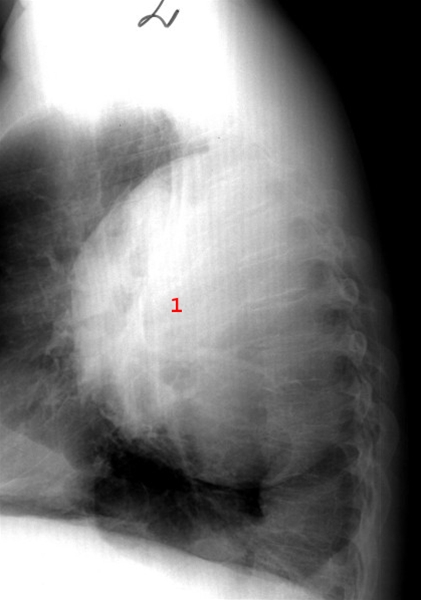

Stor lungeabsces, pusfyldt hulrum i lungevævet (1), set fra siden.